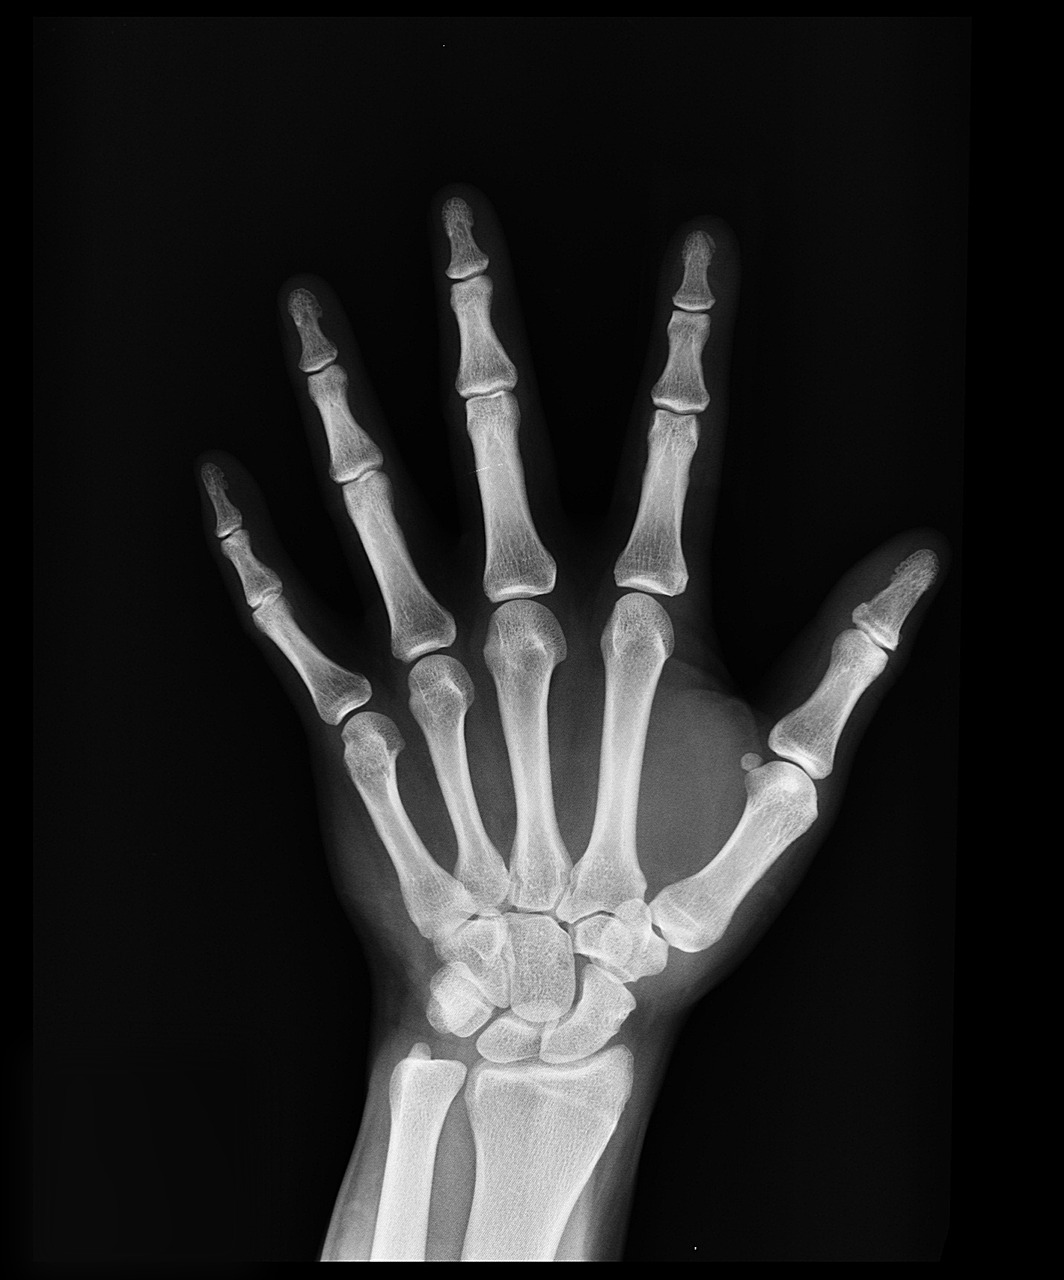

1) 방사선 촬영(X-ray)

가장 기본적인 진단 방법으로, 종양의 크기와 위치를 확인하는 데 사용됩니다. 뼈암의 초기 변화는 X-ray에서 뚜렷하게 나타날 수 있습니다.